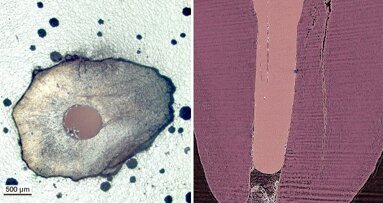

ברלין, גרמניה / אמסטרדם, הולנד: חוקרים בחנו מספר עשרות של שורשי שיניים באתר BESSY II , לפני ...